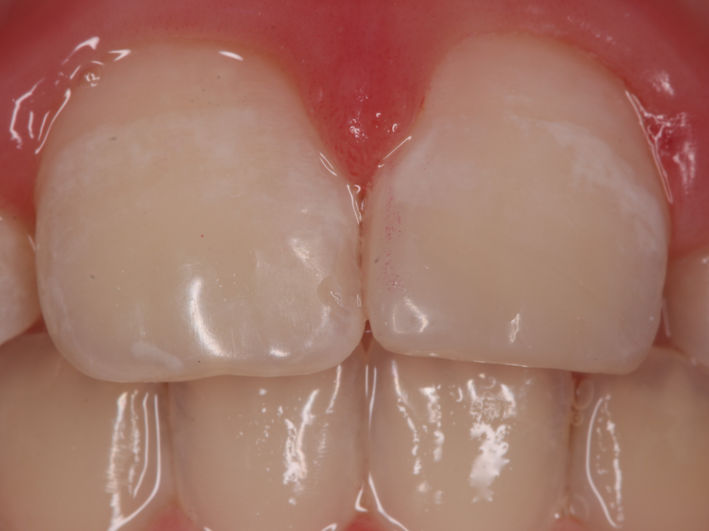

După tratamentul ortodontic și câștigarea spațiului necesar am preparat minim dintele, am luat amprentă și tehnicianul a realizat un onlay din material compozit. Acesta a fost lipit sub izolare cu digă.